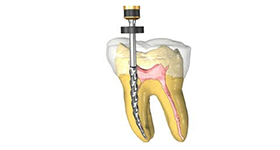

When a tooth becomes infected or damaged, root canal treatment is often the only way to save your tooth and repair the damage. Infection spreads to the bone and tissues and an abscess forms at the roots.

The treatment involves clearing the infection after numbing the tooth by a cleaning and disinfecting process of the roots. The root canals are then filled with an inert material and sealed. A crown has to be placed following the treatment to protect the tooth from further damage.